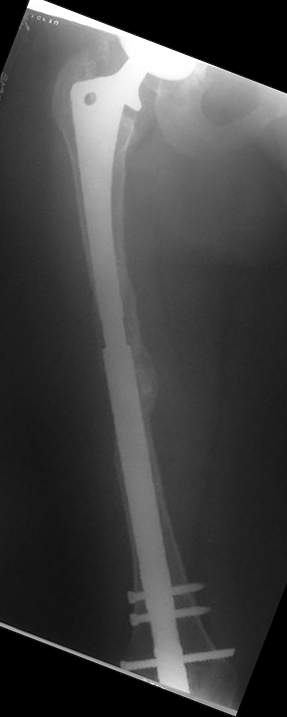

Female, rheumatoid, THA in 2003, car accident in 2006, failed plating. Nailing in Oct 2007. The nail is solid with hollow proximal part where the stem is docked. Last images are in 1 year after

nailing.

I have refreshed respect for the mighty femur and it’s incredible/remarkable ability to unite, regardless of what we do to it.

The femur responded by failure to Mennen plating (DePuy Bridge plate). So i would add that the ability to unite is realized in mechanically and biologically sound conditions.